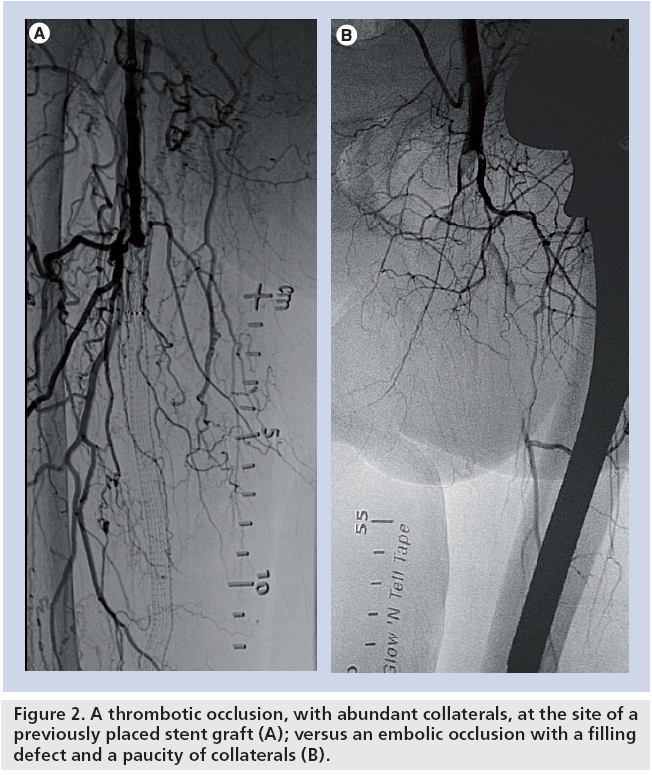

> ⭐ **Clinical Pearl**: **Embolic occlusion** shows **sharp cutoff** on angiography with **normal proximal vessel**, while **thrombotic occlusion** demonstrates **tapered narrowing** with **diffuse atherosclerotic changes** and **collateral circulation**.